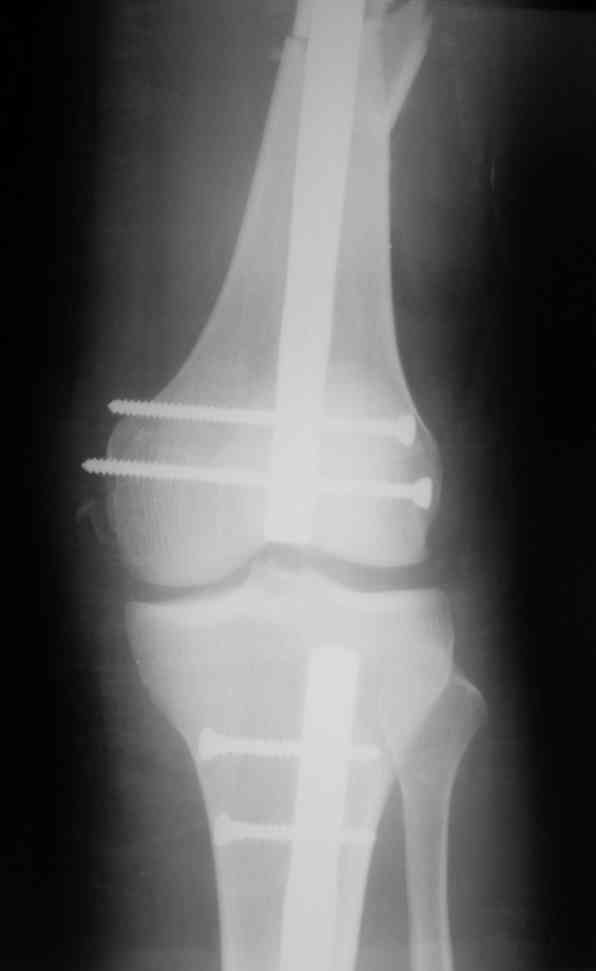

Дорогой Александр. Имею скромный опыт использования системы Fixion при

переломах плеча, бедра и тибии. Всего 18 наблюдений с сентября 2007

г.Результаты отличные. Гвоздь индивидуален для каждого медулярного

канала. Легко имплантируется как в узкий, так и в деформированный

канал. Это позволяет применять метод интрамедулярного остеосинтеза без

ненужных потерь времени операции, флюороскопии и реально снижает

крвопотерю и операционный риск. Удаление происходит без проблем.

Особенно интересны больные с ипсилатеральными переломами бедра и голени.

В отношении ранней нагрузки при спиральных переломах лучше не

торопиться. По данному случаю необходимо достигнуть исчезновения щели

между штифтом и внутреним кортексом по Rg. А так картинка прекрасная -

и длина сегмента и репозиция. Можно поздравить, коллега!